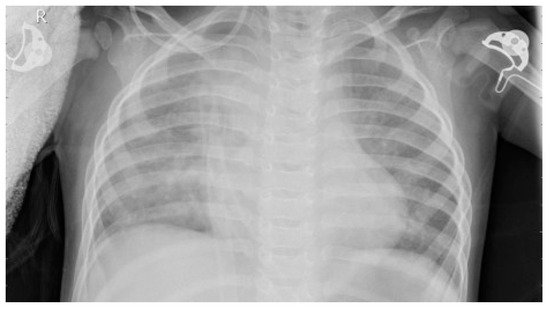

2.2. Dataset

2.4. Image Enhancement Techniques